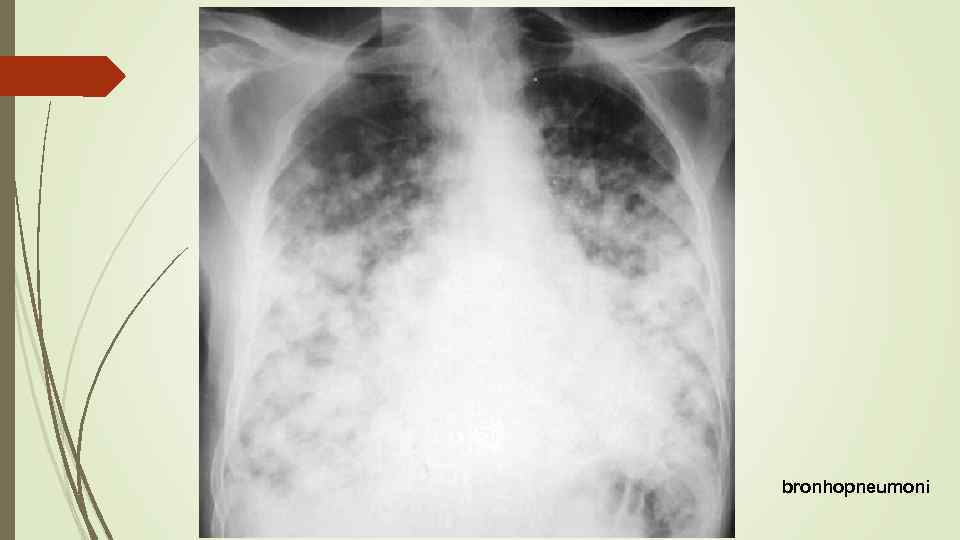

Бронхопневмония Характерно наличие двухсторонних множественных очаговых теней. Контуры очагов нечеткие, интенсивность тени небольшая. Инфильтрация неоднородна. Мелкие, малоинтенсивные очаги не всегда выявляются на снимках. Легочный рисунок усилен на всем протяжении легких. Корни расширены, не структурны. Как правило, отмечается реакция плевры, могут быть и экссудативные плевриты.

Бронхопневмония Характерно наличие двухсторонних множественных очаговых теней. Контуры очагов нечеткие, интенсивность тени небольшая. Инфильтрация неоднородна. Мелкие, малоинтенсивные очаги не всегда выявляются на снимках. Легочный рисунок усилен на всем протяжении легких. Корни расширены, не структурны. Как правило, отмечается реакция плевры, могут быть и экссудативные плевриты.

bronhopneumoni

bronhopneumoni

bronhopneumonie miliar

bronhopneumonie miliar